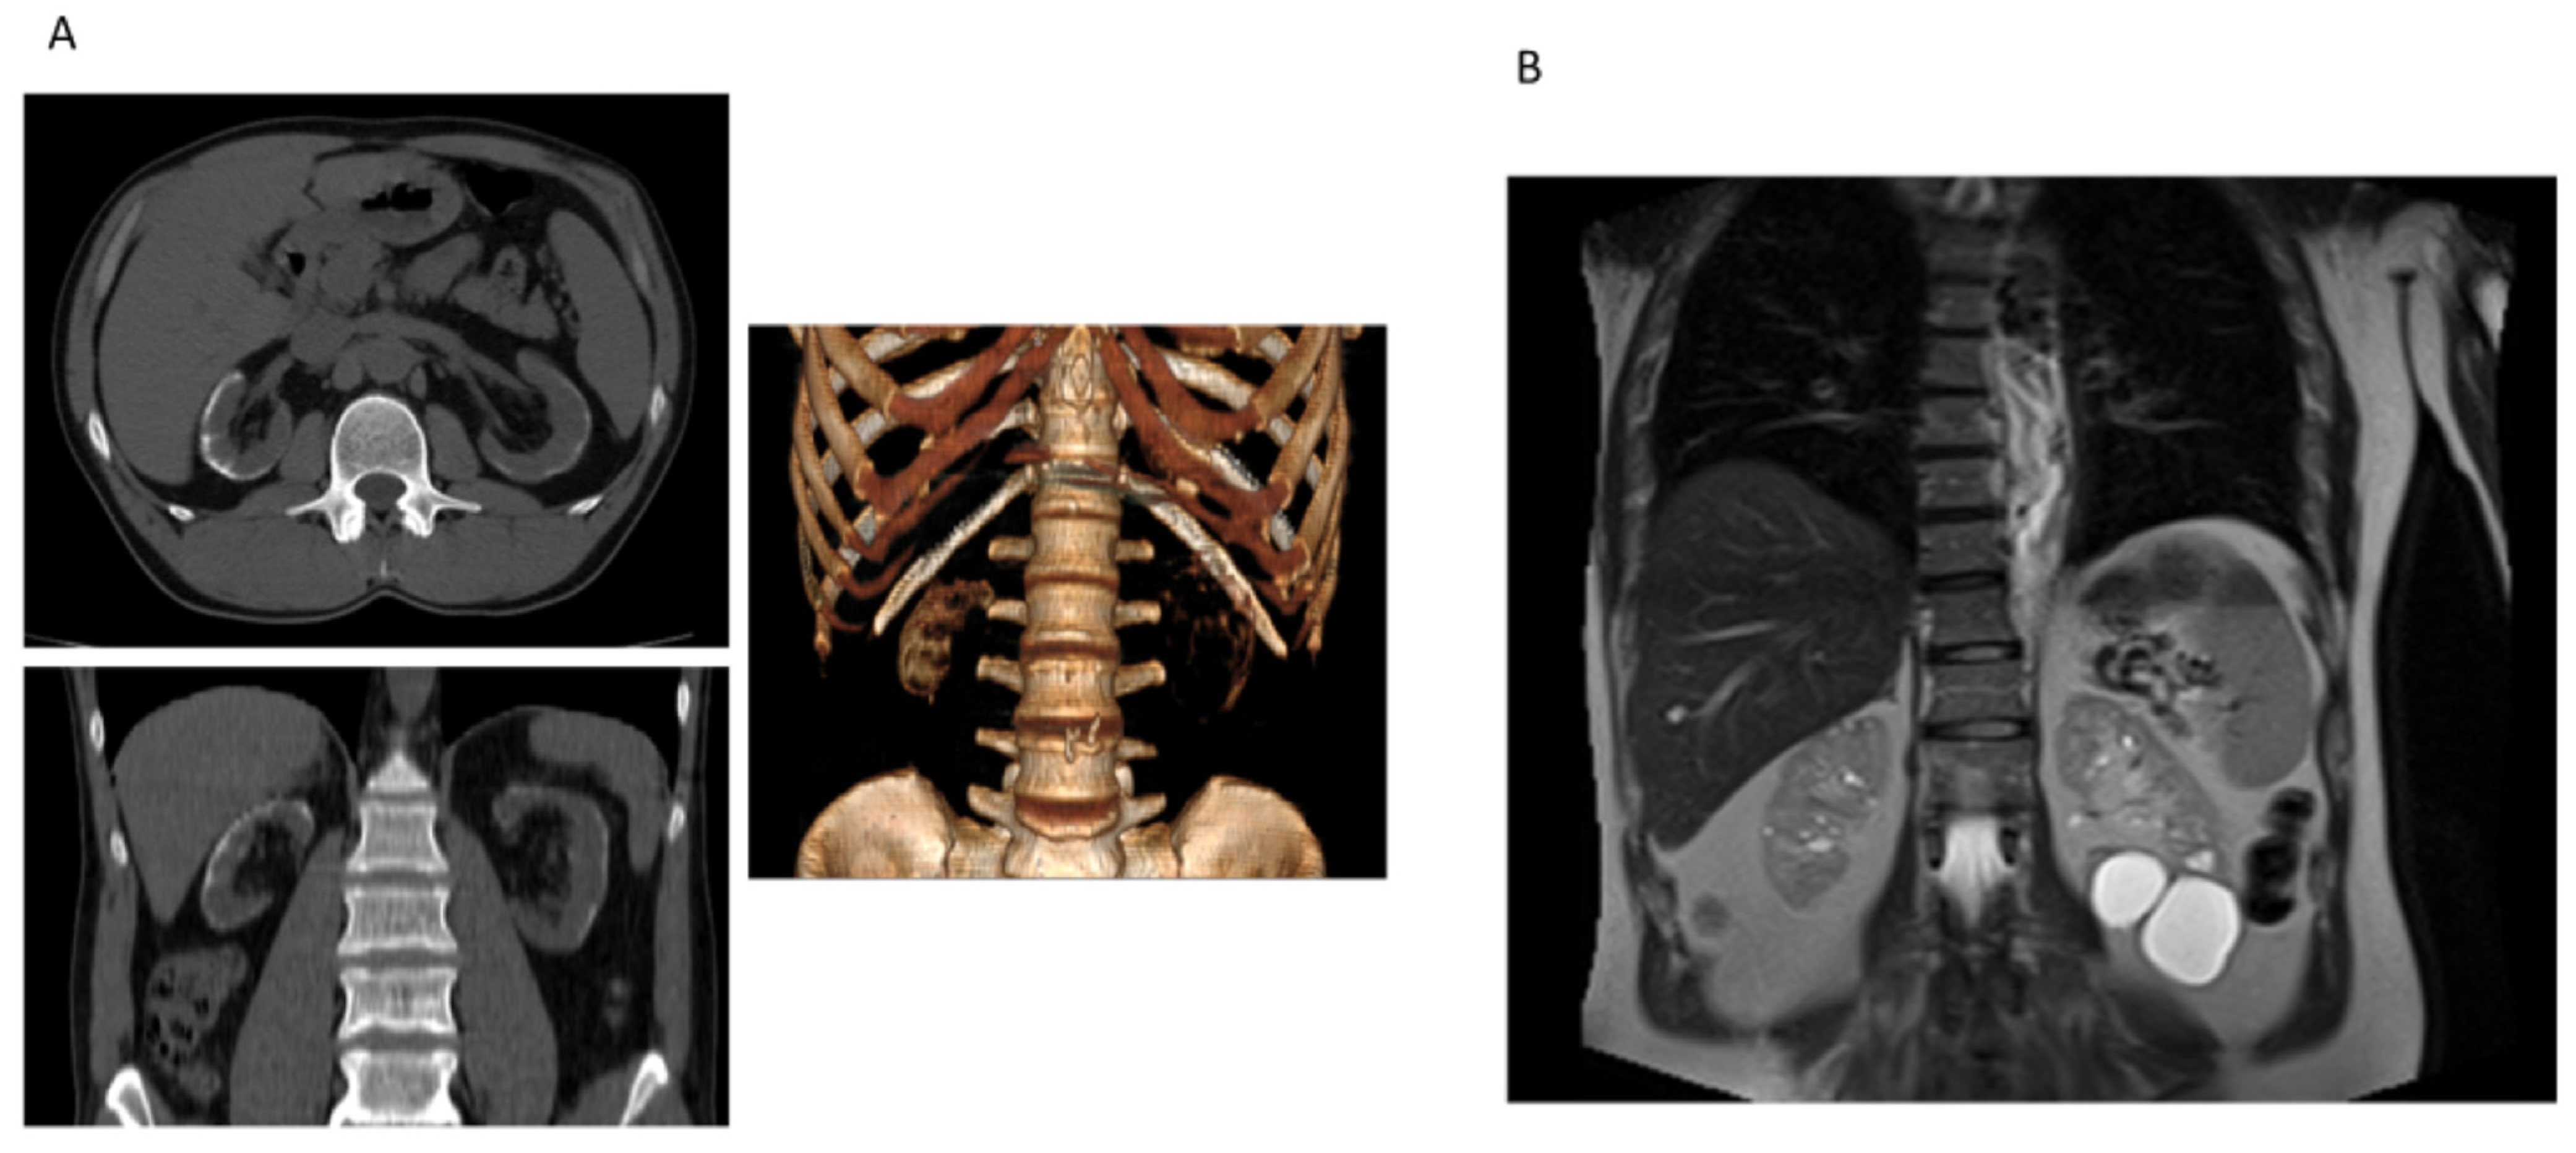

Case 2 was a 49-year-old man that referred to the hospital in emergency for epistaxis who had unremarkable personal and familial history of disease. He denied suffering from any significant morbidity; he was not under chronic medication and did not exhibit previous medical reports. On admission, high blood pressure and advanced renal dysfunction (estimated GFR of 13 mL/min/1.73 m2) were revealed. Sensorineural deafness was referred. Renal ultrasound showed a decreased size of the right kidney, with parenchymal calcifications and fetal lobulation bilaterally. The abdomen computed tomography (CT) scan confirmed cortical calcification (Figure 5). Subsequent analysis revealed that circulating parathyroid hormone (70 pg/mL), calcium (9 mg/dL, 2.25 mmol/L), and phosphate (4.1 mg/dL) levels were unremarkable considering the level of chronic renal disease. No vitamin D and/or calcium supplementation had been taken in the past. Few months later, the patient started chronic hemodialysis and, after two years, he underwent kidney transplantation. Because of the relatively young age at ESRD and the unknown cause of renal dysfunction, the patient underwent genetic analysis.

Figure 5.

(A) Case 2 computed tomography (CT), in axial (upper) and coronal (low) planes, showing cortical and circumferential calcifications. The image on the right shows that the renal cortex has a density similar to the bone, further indicating the diagnosis of cortical nephrocalcinosis. (B) Case 3 abdomen CT showing subcentimetric cysts on the right and larger cysts on the left kidney.

Case 3 was a 59-year-old male admitted to the Nephrology Unit for chronic kidney disease of unknown cause. The patient had suffered from polyuria and microhematuria since childhood; proteinuria appeared when he was thirty-one years old. In his familial history, the mother had intermittent hematuria, with normal overall renal function. His son showed hyperuricemia and a slight decline of eGFR. The proband underwent abdomen ultrasound and CT scan: the right kidney showed a reduced longitudinal diameter (10 cm) and subcentimetric cysts and four large cysts were detected on the left kidney (Figure 5B). Increased echogenicity with reduced corticomedullary differentiation were evident on ultrasound. The representation of the vascular tree was reduced. Because of the familiar history of renal disorders, the genetic analysis of the patient and his son was performed.